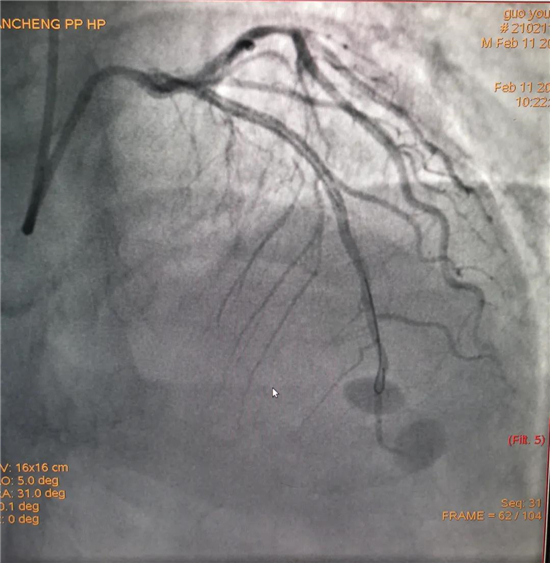

除夕,郭先生無明顯誘因突發(fā)胸痛,120急救人員到達現(xiàn)場,心電圖顯示:竇性心律完全性束支傳導(dǎo)阻滯。信息立刻發(fā)送到胸痛中心介入微信群中,心內(nèi)科值班醫(yī)生初步診斷為急性廣泛前壁心肌梗死,必須盡快進行急診支架治療,開通血管。值班醫(yī)生電話指導(dǎo)院前治療,并立即啟動胸痛綠色通道,24小時備班的介入治療團隊立即到位,9:30患者被送到導(dǎo)管室行冠脈介入診療,9:40急診PCI手術(shù)隨之開始,冠脈造影檢查提示左前降支閉塞,植入支架,堵塞的血管被順利打通,患者癥狀緩解,手術(shù)非常成功,10:20患者被送往病房進一步治療。